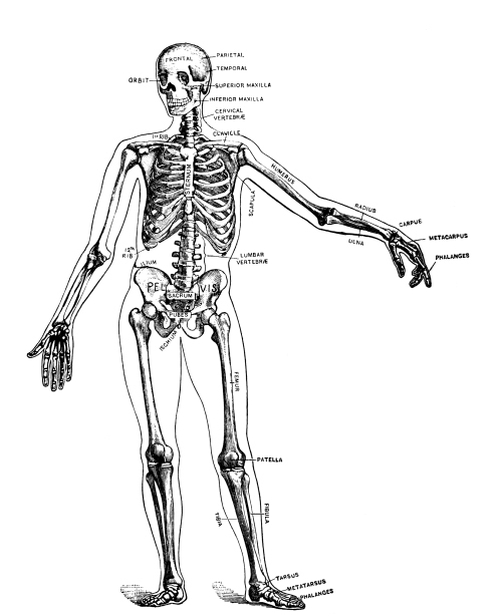

The human skeleton (Lewis).

The human skeleton (Lewis).

Classification and Function of Bones.—There are in the body some two hundred bones, which may be classified as long, short, flat, and irregular. Occasionally an irregular bone develops in a fontanelle, the membranous opening at the juncture of the sutures of the skull. This is known as a Wormian bone. It is not, however, included in the two hundred, as are not the sesamoid bones or bones developed in tendons, with the exception of the patella or knee-cap.

Long bones are developed in cartilage and consist of a shaft, two extremities, and various processes. They are more or less curved to give them strength and grace. They serve as supports and act as levers for purposes of motion and the exercise of power. Since a hollow cylinder is just as strong as a solid one of the same size, the weight coming only on the outer shell, the great bones which are accountable for weight and which need to be light themselves have hollow shafts, composed chiefly of compact tissue with a central medullary canal. The ends, however, are expanded in order to make better connection at the joints and to afford broad surfaces for muscular attachment, cancellous tissue being used in them for lightness and strength. The large spongy ends also give elasticity and lessen jar, and by bringing the tendons to the bone at a greater angle increase their effectiveness. Blood is brought to the long bones not only by the vessels of the periosteum but by the medullary artery, which penetrates the compact tissue by the nutrient foramen and divides into an ascending and a descending branch. [Pg 20]

Short bones are spongy throughout. They are used for strength and where little motion is required.

Flat bones are composed of two thin layers of compact tissue with a varying amount of cancellous tissue between, and are for protection and muscular attachment. The cancellous material between the two layers or tablets of the skull is called the diploë.

As a whole the bony framework serves to keep the soft parts in place, to support and protect them, and to aid in locomotion. The bones of the head and trunk support and protect organs; those of the arms are for tact and prehension; those of the lower extremities are for support and locomotion.